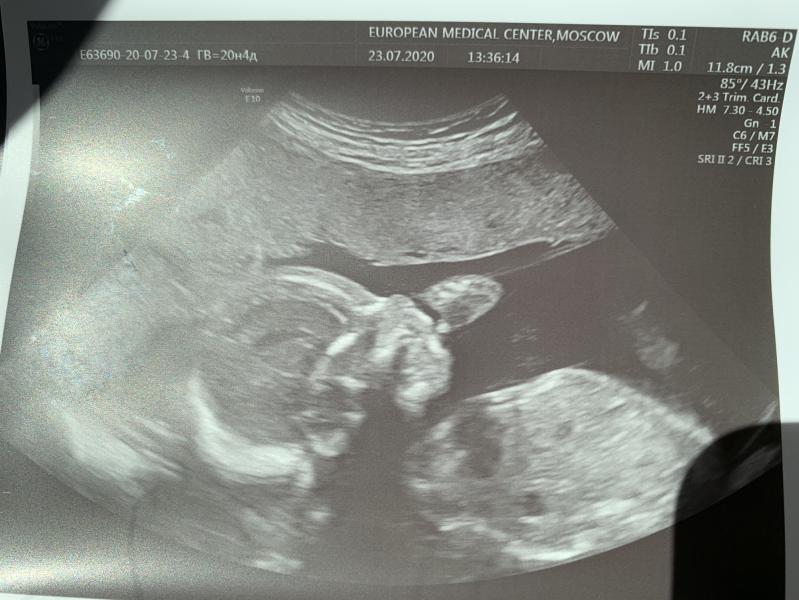

Наши 20 неделек и очередной поход на узи.

Мои пельмешки нажирают щечки, лежат оба в головном, у мамы в лобке... 😅 из за чего моя походка - аля только слезла из позы наездницы😅😅

Дети еще такие крохи, а уже такие характерные! Не любят они , когда их беспокоят. На узи закрывают лицо ручками, отворачиваются. Наш папа никак не Может поймать пинки, кладет руку, и они тут же затихают 🤷🏻♀️